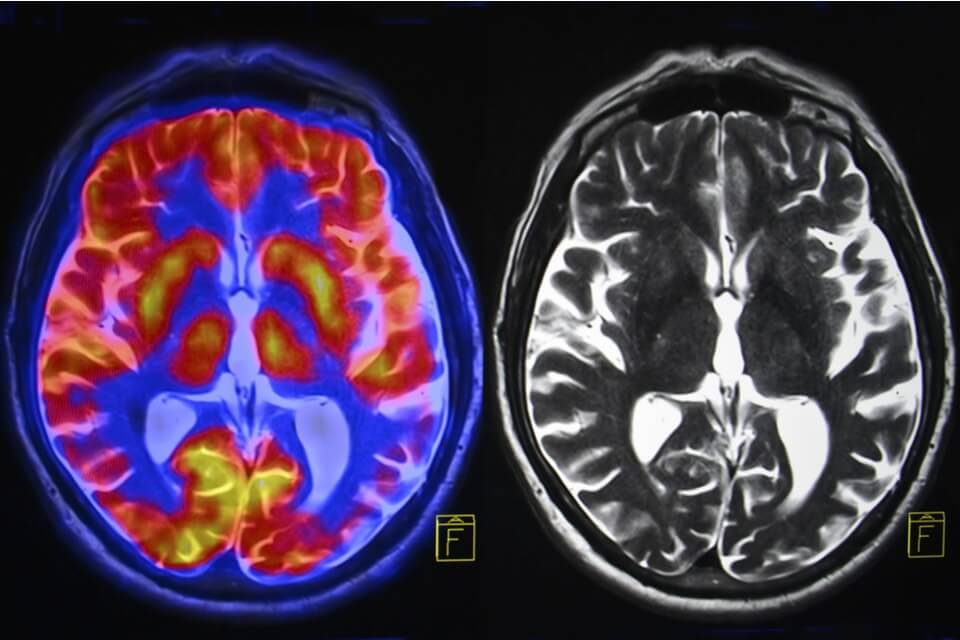

VITT is characterised by platelets, key elements of the body’s clotting system, clumping together. This leads to blockage of blood flow in the veins and bleeding risk due to a lack of platelets available for normal clotting processes. The most common and severe manifestation of VITT is cerebral venous thrombosis, in which veins draining blood from the brain become blocked leading to severe congestion and very high pressure in the brain.

This poorer outcome is explained at least in part because the abnormal blockage of veins is much more extensive in this condition, with more veins blocked both in the head and elsewhere in the body.